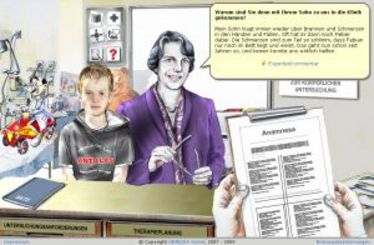

Probanden gesucht

Probanden gesucht